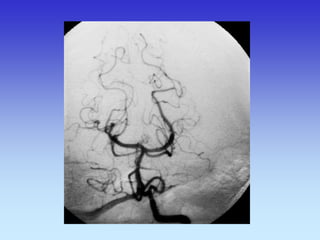

METODE PRIKAZA KRVNIH ŽILA

•UZ-DOPPLER

•DSA

•CTA

•MRA

VASKULARNA OPSKRBA WILLIS-ijev prsten

a. cerebri ant.

a. cerebri media

a. cerebri post.

A-V MALFORMACIJA